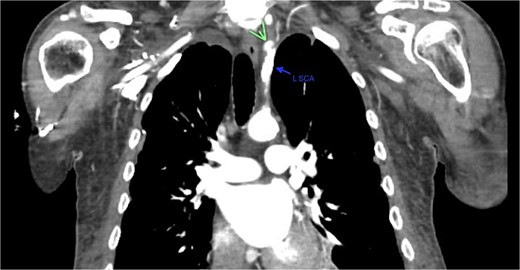

A 67-year-old male with a medical history significant for hypertension, diabetes, coronary artery disease, carotid artery stenosis, osteoarthritis, and 50 pack-year smoking history presented initially to an orthopedic surgery office for evaluation of left shoulder pain after exercising. The patient was found to have an underlying rotator cuff injury and was subsequently treated with cortisone injection. The patient subsequently developed septic arthritis, ultimately requiring incision and drainage of the abscess and resection of the sternoclavicular joint, partial first rib, and partial clavicle. The patient required multiple washouts and debridement procedures, ultimately leading to septic shock and bacteremia requiring close observation in the surgical intensive care unit. A computed tomography angiogram (CTA) of chest was performed at the time and revealed a subcentimeter penetrating ulcer, arising from the proximal left subclavian artery likely secondary to surgical trauma, which was observed nonoperatively given the patient critical status in the intensive care unit (ICU) (Figs 1 and 2). During the ICU course, the patient developed left upper extremity swelling A left upper extremity duplex ultrasound subsequently revealed a nonocclusive deep vein thrombosis of the subclavian vein and also showed resolution of a pseudoaneurysm (PSA) of the subclavian artery. The patient was started on anticoagulation at this time for a deep vein thrombosis (DVT). The patient was ultimately discharged upon resolution of his acute infection to a rehabilitation facility. During the third-month follow-up office visit, the fistulous connection between the subclavian artery and vein was found incidentally on left upper extremity duplex ultrasound (Fig. 3). Physical exam of the patient was otherwise unremarkable with palpable upper extremity pulses and the patient did not appear to have any symptoms related to the fistula including upper extremity swelling or open wounds. The patient was scheduled for an elective repair of the fistula via endovascular stent graft placement. The patient was brought to the operating room, and the radial artery was accessed with a micropuncture device. Radial artery access was our choice to intervene given the location of fistula. When left upper extremity angiography was performed, it revealed a blush of contrast from proximal subclavian artery, revealing a small fistula between subclavian artery and subclavian vein (Fig. 4). Subsequently, a 6 × 29 mm balloon-mounted stent graft was used to cover the fistula. Completion angiography was performed showing adequate seal with resolution of the fistula (Fig. 5). The patient tolerated the procedure well and was subsequently discharged from the hospital the same day. He was started on antiplatelet therapy post-operatively and continued oral anticoagulation for the DVT. The patient was seen in the office at 3-month follow-up, where a repeat duplex ultrasound revealed normal waveforms and velocities throughout the left arm. He was also seen in the office recently, and he is doing well with no new complaints.

Demonstration of pseudoaneurysm of the proximal left subclavian artery on axial image (green arrow: L SCA PSA, blue arrow: left subclavian artery).